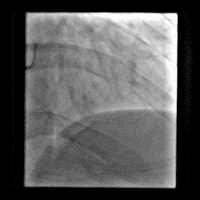

冠脉造影

造影时间: 入院当天03:35~03:52。

造影结果(一): 前降支近段闭塞,回旋支中远段90%狭窄。

造影结果(二): 右冠中段闭塞。

造影结论及应对策略: 前降支近段闭塞,回旋支中远段90%狭窄,右冠中段闭塞,未行左室造影。病变血管:前降支;回旋支;右冠。与家属沟通,同意行PCI。